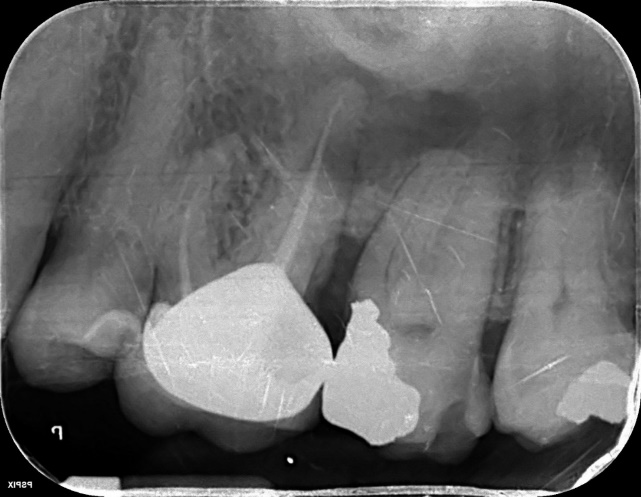

Lower Molar x2 curved roots Primary Root canal treatment and dental crown/rebuild